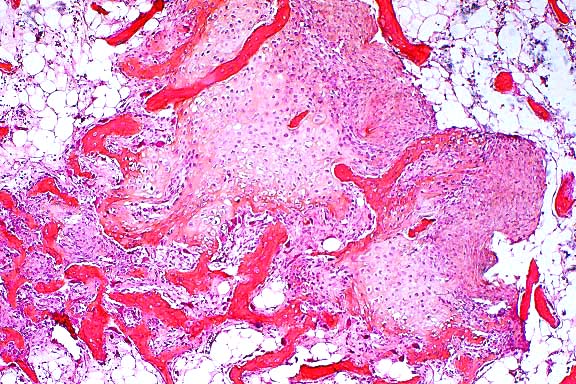

4x

obj

10x

- Case 20-1. Bone. At the margin of the necrotic sequestra

(left), which extends through the growth plate, there is a mixture

of degenerate neutrophils, fibrin, edema, and cell debris (right).

- Case 20-1. Bone. The necrotic bone (right), and marrow

is being replaced by neutrophils, macrophages and fibroblasts

forming collagen (center & left).